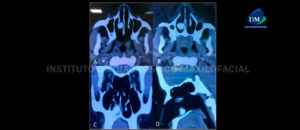

La dentición ectópica intranasal es una entidad clínica bastante rara. Sin embargo, es importante identificar estos dientes, que puede ser supernumerario, deciduo o permanente, para